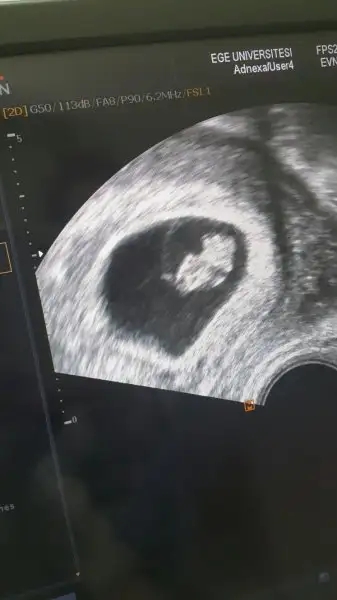

Buda benim bebişim ama kaç mm neyin nesi söylemedi doktor..fotografta vermediler biz cep telden cektk